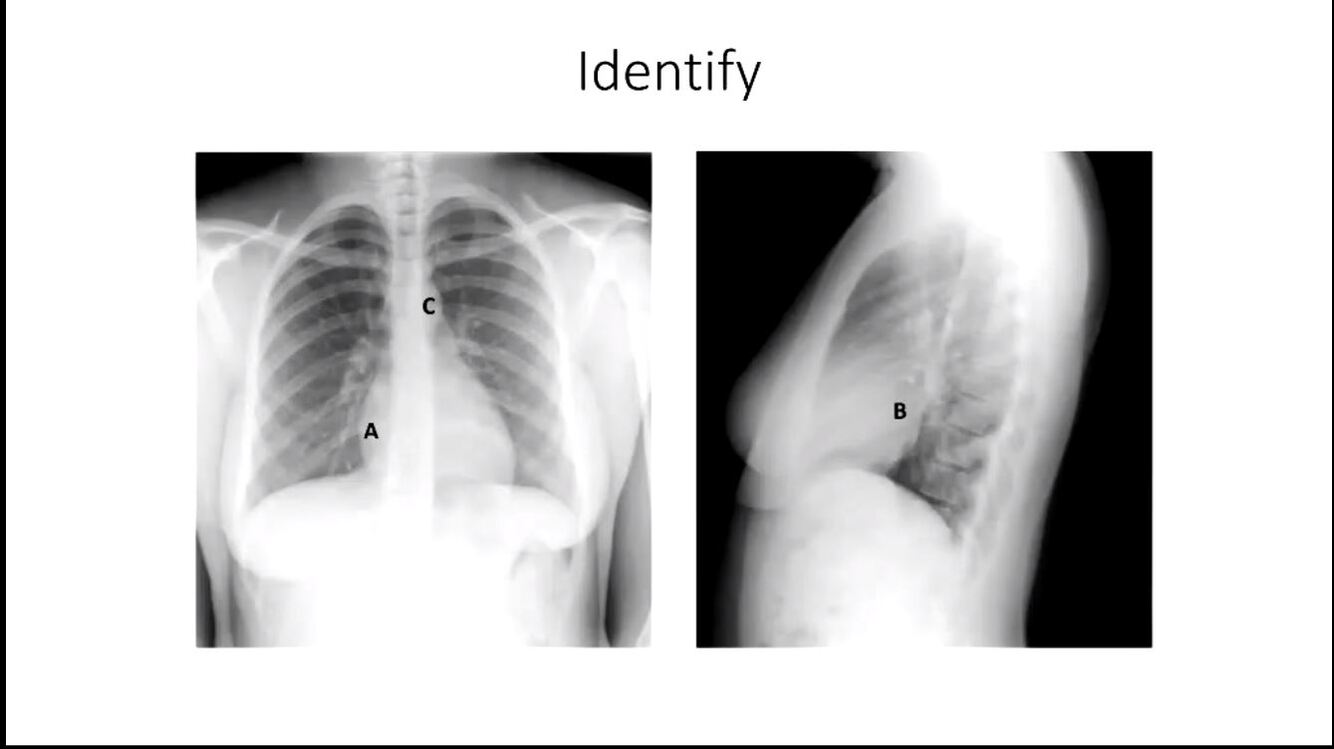

identify

A right atrium

B left atrium

C aortic knuckle